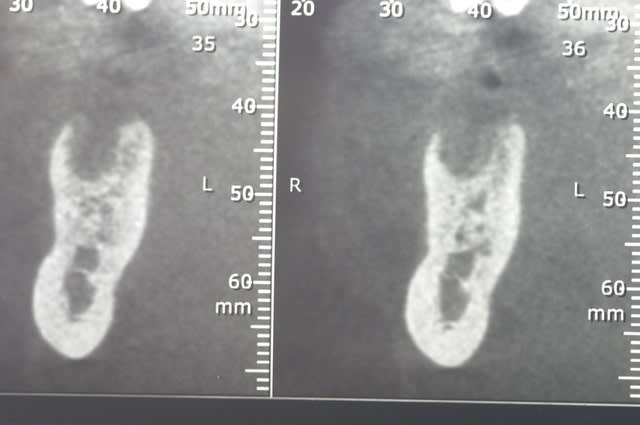

ci joint les photos des coupes scanner d'un patient à qui j'ai proposé de poser un implant afin de remplacer la 36. sur les coupes, on vois nettement le dédoublement du NAI.

Après discussion avec le radiologue qui ni avait pas fait allusion dans son compte rendu, celui-ci me dit que le canal le canal ne contient que quelques filet nerveux (je ne sais pas comment il peut voir cela..) et que je peux passer au travers sans problèmes.

je voulais savoir si certains d'entre vous avaient déjà traversé des branches accessoires du NAI aussi volumineuse radiologiquement.